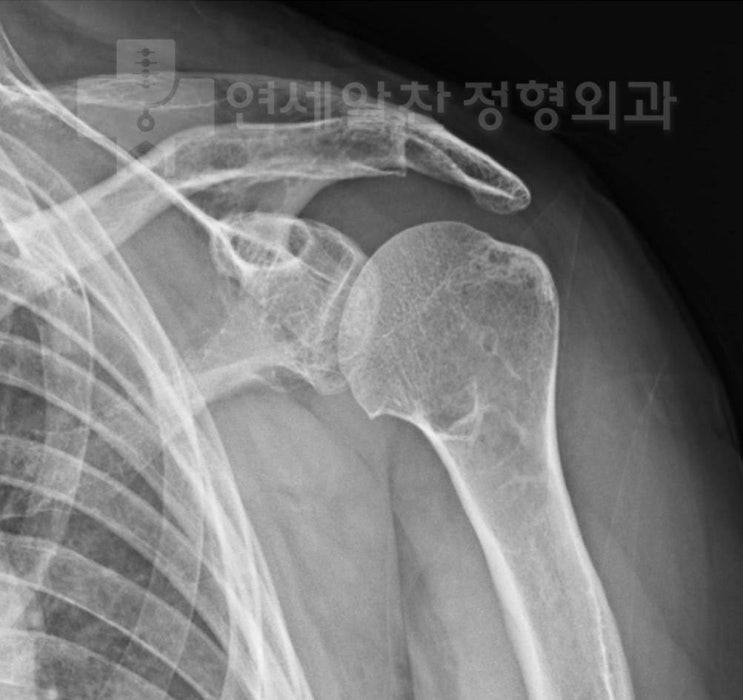

어깨 퇴행성 관절염을 동반한 회전근개파열에서 연골 연마관절성형술(abrasion arthroplasty) 및 회전근개 봉합술

71세 여자환자로 좌측 어깨 통증을 주소로 내원하였다. 환자는 6개월전 본원에서 양측 슬관절 퇴행성 관절...